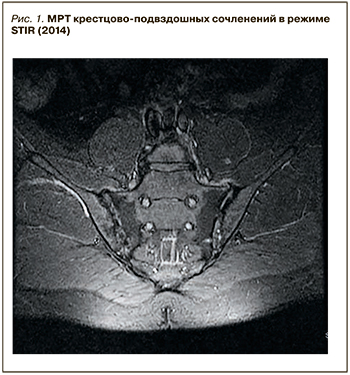

При дообследовании исключены АС и ревматоидный артрит по результатам клинического, лабораторного (нормальные значения С-реактивного белка (4 мг/л), ревматоидного фактора, скорости оседания эритроцитов) и инструментального (отсутствие изменений по результатам МРТ крестцово-подвздошных сочленений (в режимах Т1, STIR) и рентгенографии таза) исследований (рис. 1). Методом УЗИ костно-мышечной системы выявлен двусторонний энтезит паховой связки. Учитывая наличие суставного синдрома, энтезита, псориаза, дактилита в анамнезе, а также отрицательного ревматоидного фактора был выставлен диагноз ПсА (соответствие критериям CASPAR, 2009).